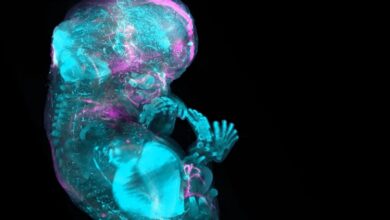

Científicos crean mapa del cuerpo humano célula por célula

El cuerpo humano contiene entre 36 y 37 billones de células, y los investigadores están determinando dónde vive cada una…